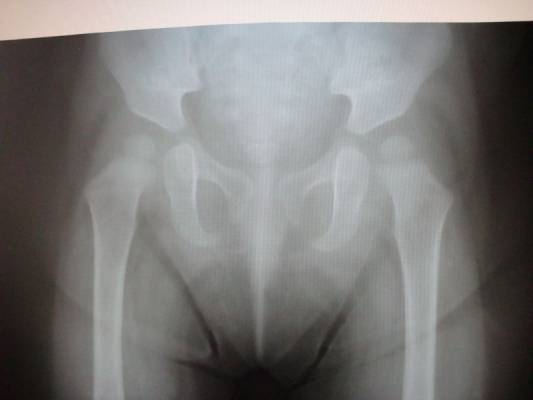

Альбом ДИСПЛАЗИЯ ТАЗОБЕДРЕННЫХ СУСТАВОВ ?. Фото "уточнение диагноза "Дисплазия тазобедренных суставов" ребенку 1 год." 35.9 k (800x600) DSC04878.JPG

уточнение диагноза "Дисплазия тазобедренных суставов" ребенку 1 год.

АльбомДИСПЛАЗИЯ ТАЗОБЕДРЕННЫХ СУСТАВОВ ?